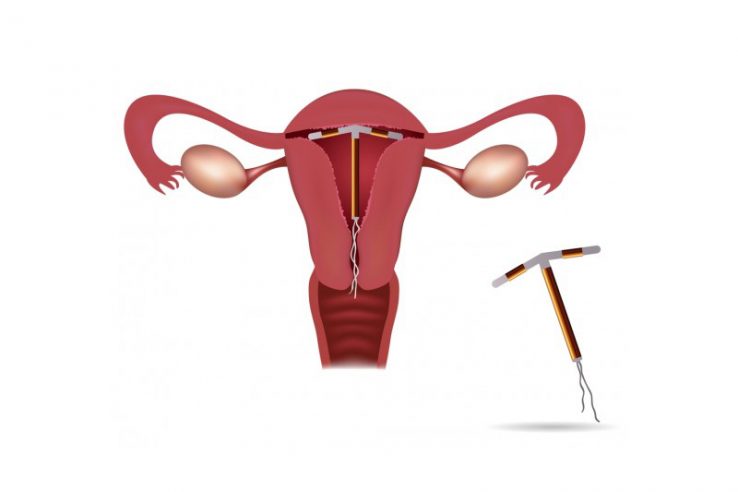

Infertility is a condition affecting millions of people worldwide, often in silence and solitude. For many couples, the path to parenthood is not always straightforward, and understanding how common infertility…